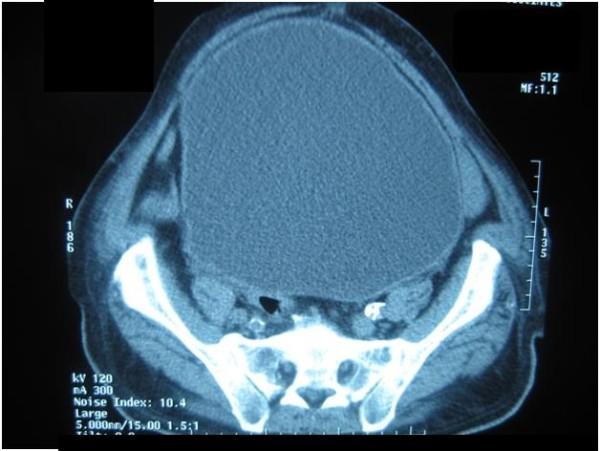

An 83-year-old man of African descent presented with constipation and bilateral lower limb edema. A huge abdominal mass was evident which was a large, distended urinary bladder confirmed by computed tomography. Promptly after urethral catheterization, both constipation and lower limb edema resolved.

一名83岁非洲裔男性因便秘和双侧下肢水肿就诊。可见一个巨大的腹部肿块,计算机断层扫描证实为一个巨大的膨胀膀胱。尿道插管后,便秘和下肢水肿迅速缓解。

https://cdn.ncbi.nlm.nih.gov/pmc/blobs/5273/3398309/9ea68a8857af/1752-1947-6-34-1.jpg